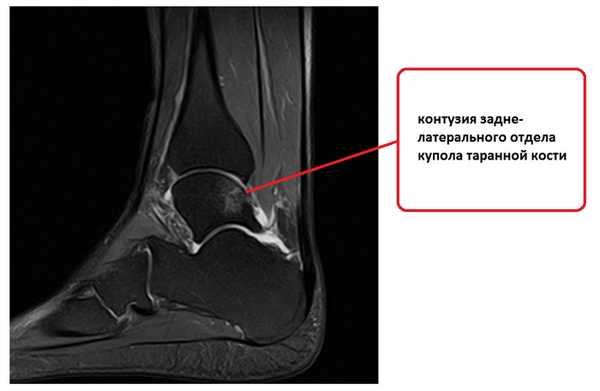

На этом этапе пациентка лечилась по стандартному сценарию «растяжение голеностопа». Носила ортез, мазала голеностоп вольтареном и лиотоном, разгружала его при помощи трости. Но в связи с длительно сохраняющимся болевым синдромом было выполнено МРТ, при котором диагностирован застарелый разрыв передней таранно-малоберцовой связки, пяточно-малоберцовой связки правого голеностопного сустава, контузионное повреждение латеральных отделов таранной кости.

В данном случае выбор хирургического вмешательства шёл между стандартной процедурой Бростром в модификации Голда или пластикой аутосухожилием. Так как ранее пациентке оперативные вмешательства не выполнялись, можно было попробовать стандартную операцию по методике Бростром, а пластику оставить в качестве «запасного метода». Но для получения более стабильной конструкции учитывая выраженность нестабильности, длительную историю заболевания, наличие контузионного повреждения купола таранной кости было принято решение о проведении пластики с использованием аутотрансплантата нежной мышцы.